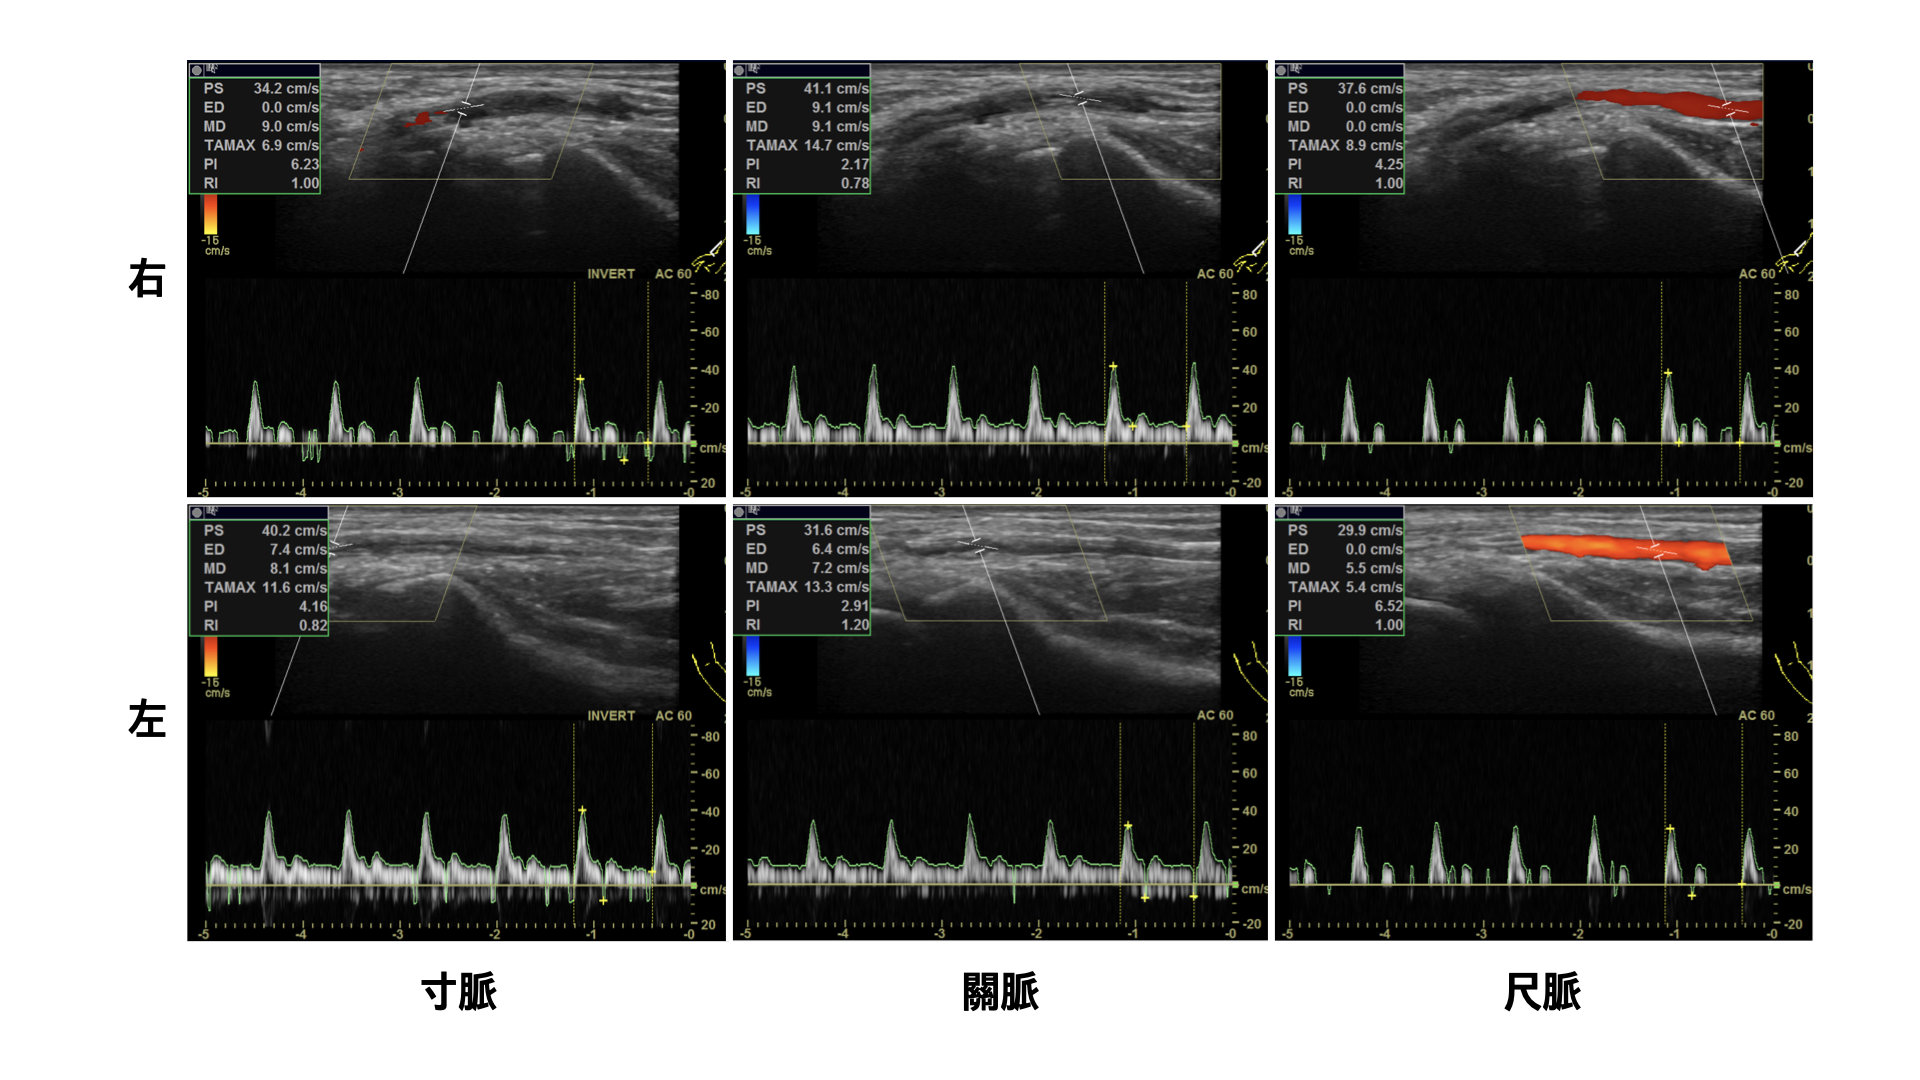

초음파 영상 진단장치를 활용한 氣口脈(요골동맥) 검사

‍